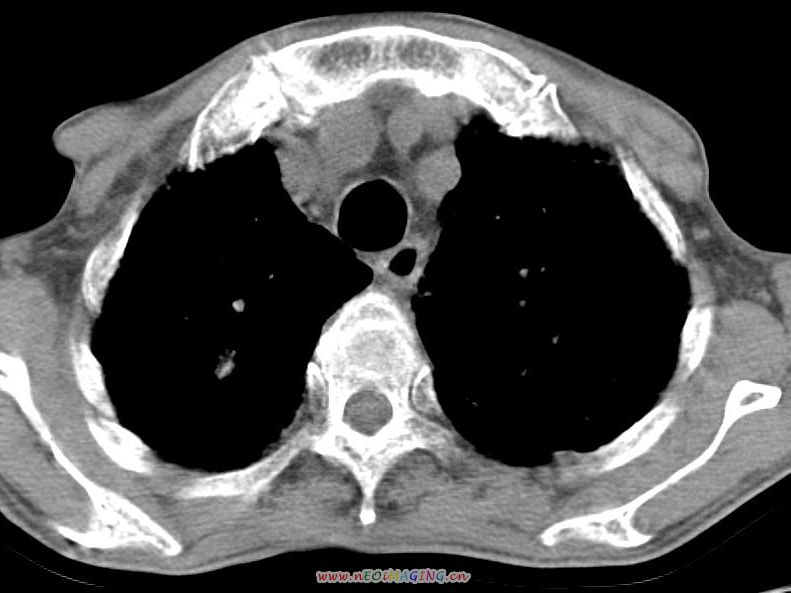

患者咳嗽月余,高热数天,咳黄色稍脓痰。

双肺野分布多个小结节状高密度影,其内散在斑片状模糊影,气管。支气管通畅,纵隔内淋巴结钙化,胸膜局限性增厚粘连,胸腔少量积液。结合病史考虑结核并感染的可能性大,胸膜炎并积液。肺泡癌待排。

纵隔内见钙化的淋巴节,上肺见钙化灶,双肺均匀弥漫分布小结节影,边缘较清楚,能不能考虑是在矽肺的基础上并发的结核和感染,请详细了解病史结合临床.